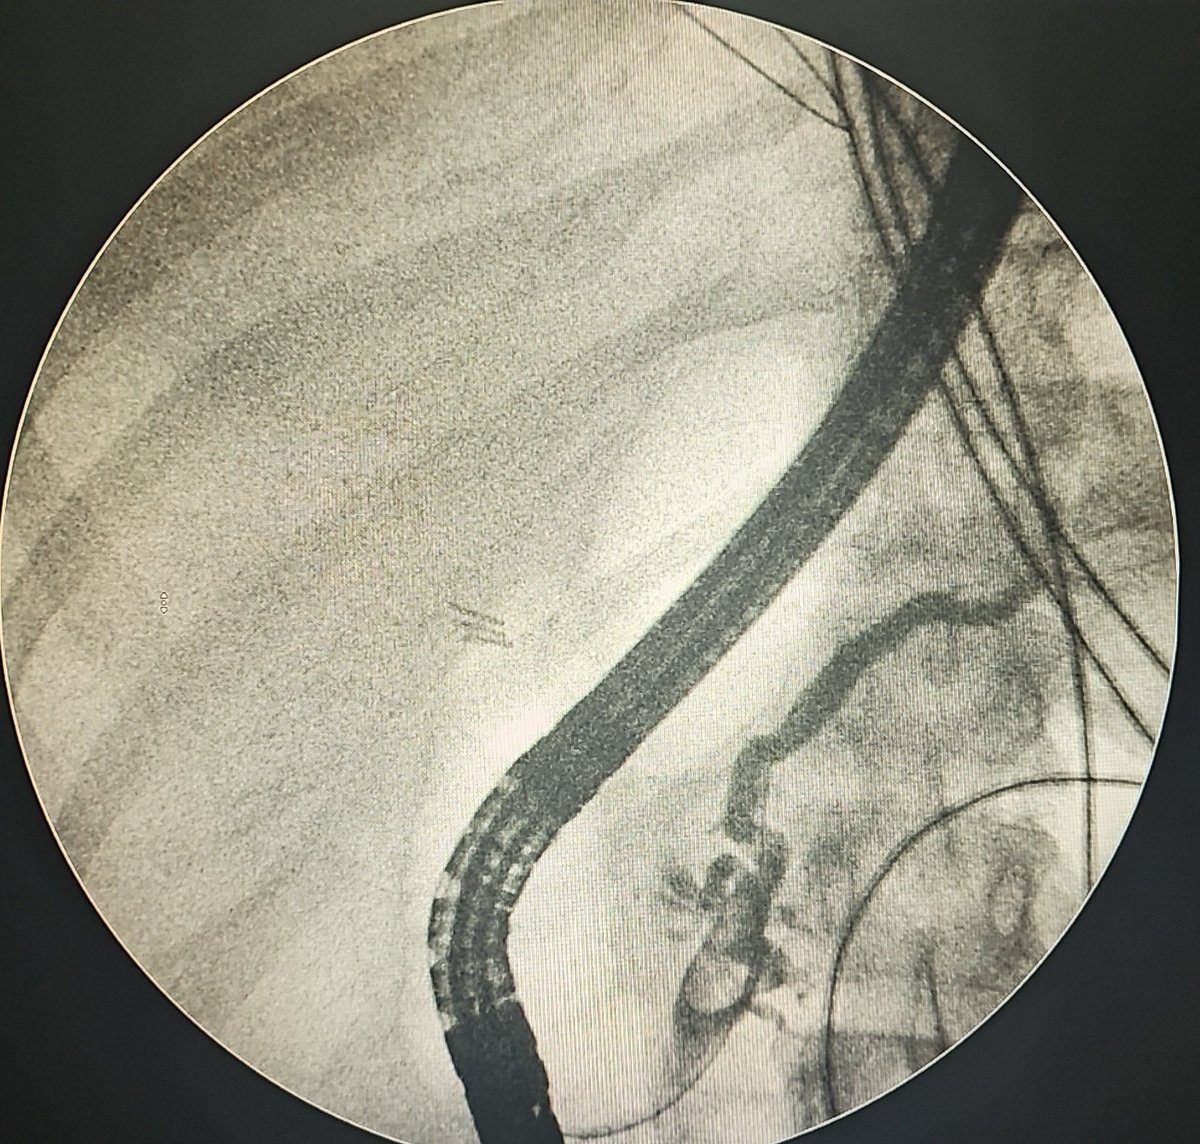

🙍♀️30s Lap CCx➡️CBD injury➡️Open repair 2 wks on, drain output ~400ml/d Pt toxic #ERCP 👉Wire keeps going into collection, cannot negotiate into intrahepatic ducts 👉Contrast - same ??CBD ligated #EUS RZV🙅♂️: Periph ducts decompressed+pneumobilia Options #GITwitter #Surgery?